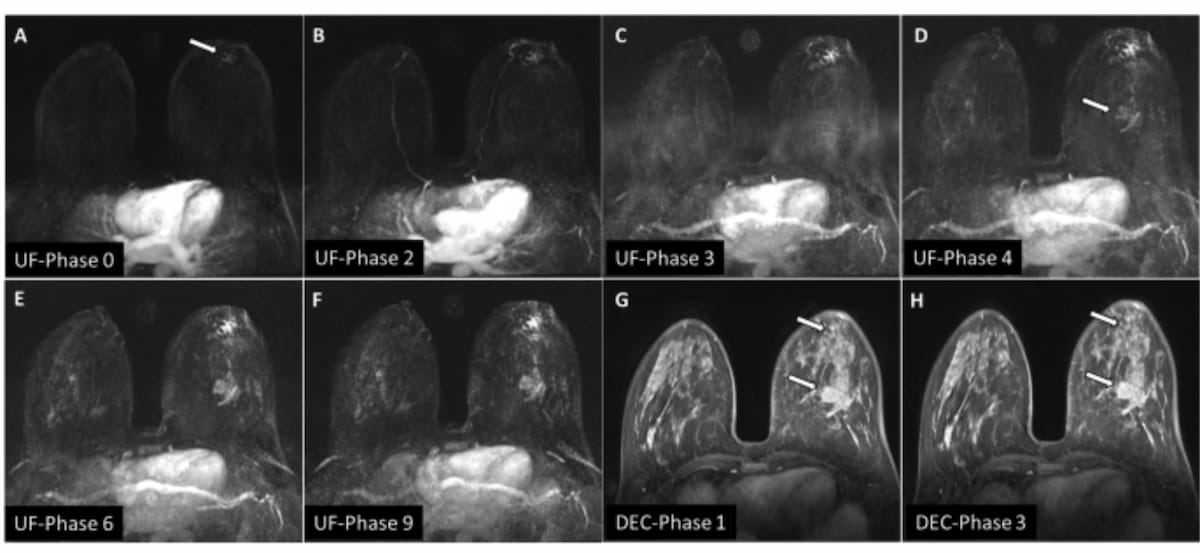

What New Prospective Research Reveals About Ultrafast Breast #MRI diagnosticimaging.com/view/new-prosp… American College of Radiology ARRS RSNA Society of Breast Imaging SBI RFS UCSF Imaging Mayo Clinic Radiology OHSU Radiology Stanford Radiology Radiology of USC UCLA Radiology UC San Diego Rad Med #radiology #RadRes